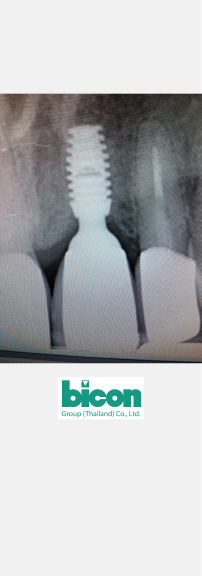

The second case was implant restoration on teeth 16. He also used Bicon implant system for this case. The restoration was created from composite on particular abutment of Bicon system. The remarkable thing was he could finish prosthesis installation within two minutes! The patient was very satisfied with the perfect result.